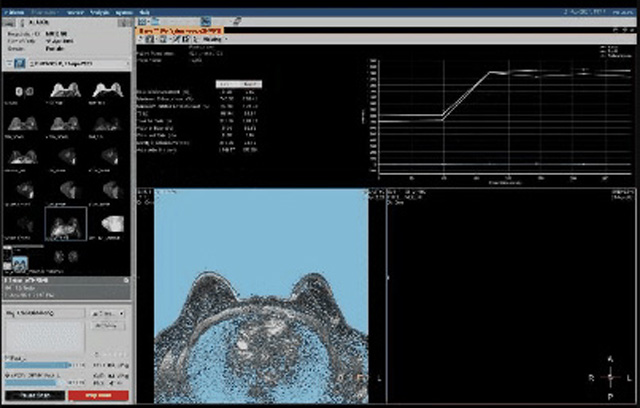

乳腺B超检查无辐射,对囊性病变敏感,可以实时观察病灶。超声引导活检跟手术前的定位。就是它对于微小的钙化查出率比钼靶稍微差点。磁共振MRI检查也是是没有辐射的,对备孕跟已经怀孕的人士比较友好。不用担心这个辐射影响胎儿问题。对乳腺病灶敏感性较高,致密乳腺病灶、乳腺癌的复发,准确鉴别囊性及实性病变。可以帮助临床医生判断恶性、良性病变。但是MRI磁共振对微小钙化不明显,微钙化还是钼靶靠谱点。检查时间比较长,有伪影的影响。费用相对B超,钼靶高很多。